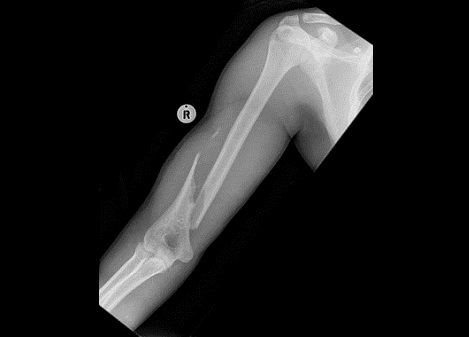

Fig10. - Humerus fracture.

Fig10. - Treated with open reduction and internal fixation.